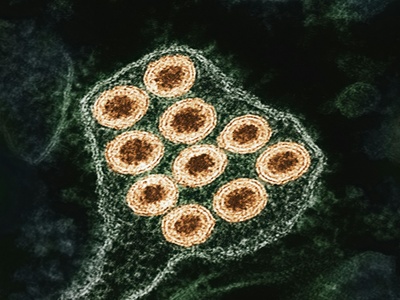

Hepatitis B

Hepatitis B can cause acute and chronic liver disease including cirrhosis and liver cancer; symptoms include jaundice and abdominal pain. Spread through blood and sexual contact. Effective vaccine prevents infection; antiviral treatments manage chronic infection.

Hepatitis C

Hepatitis C often causes chronic liver infection, sometimes progressing to cirrhosis and cancer; many people are initially asymptomatic. Transmitted mainly by blood exposure. No vaccine exists, but highly effective antiviral cures are available for most patients.